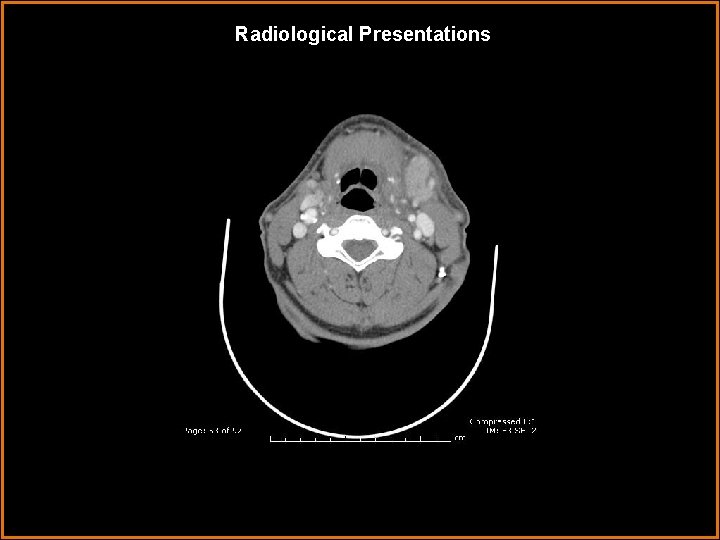

Radiological Presentations

Findings and Differentials Findings: Markedly enlarged, enhancing left submandibular gland with a large 1. 1 cm stone in Wharton’s duct. Differentials: • Submandibular venous vascular malformation – lobulated, heterogenously enhancing mass. • Sialosis – painless bilateral enlargement of salivary glands, usually the parotid glands. Associated with diabetes, obesity, and alcoholism. • Kuttner tumor – pseudomass of salivary gland associated with calcification.

Diagnosis Sialadenitis caused by sialolithiasis.